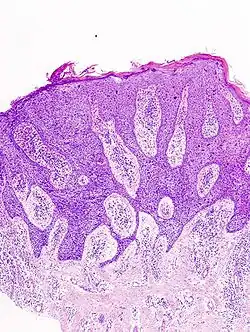

In situ disease

Bowen's disease is essentially equivalent to and used interchangeably with cSCC in situ, when not having invaded through the basement membrane.[12] Depending on source, it is classified as precancerous[13] or cSCC in situ (technically cancerous but non-invasive).[48][49] In cSCC in situ (Bowen's disease), atypical squamous cells proliferate through the whole thickness of the epidermis.[12] The entire tumor is confined to the epidermis and does not invade into the dermis.[12] The cells are often highly atypical under the microscope, and may look more unusual than the cells of some invasive squamous-cell carcinomas.[12]

-

cSCC in situ, high magnification, demonstrating an intact basement membrane.[12] -